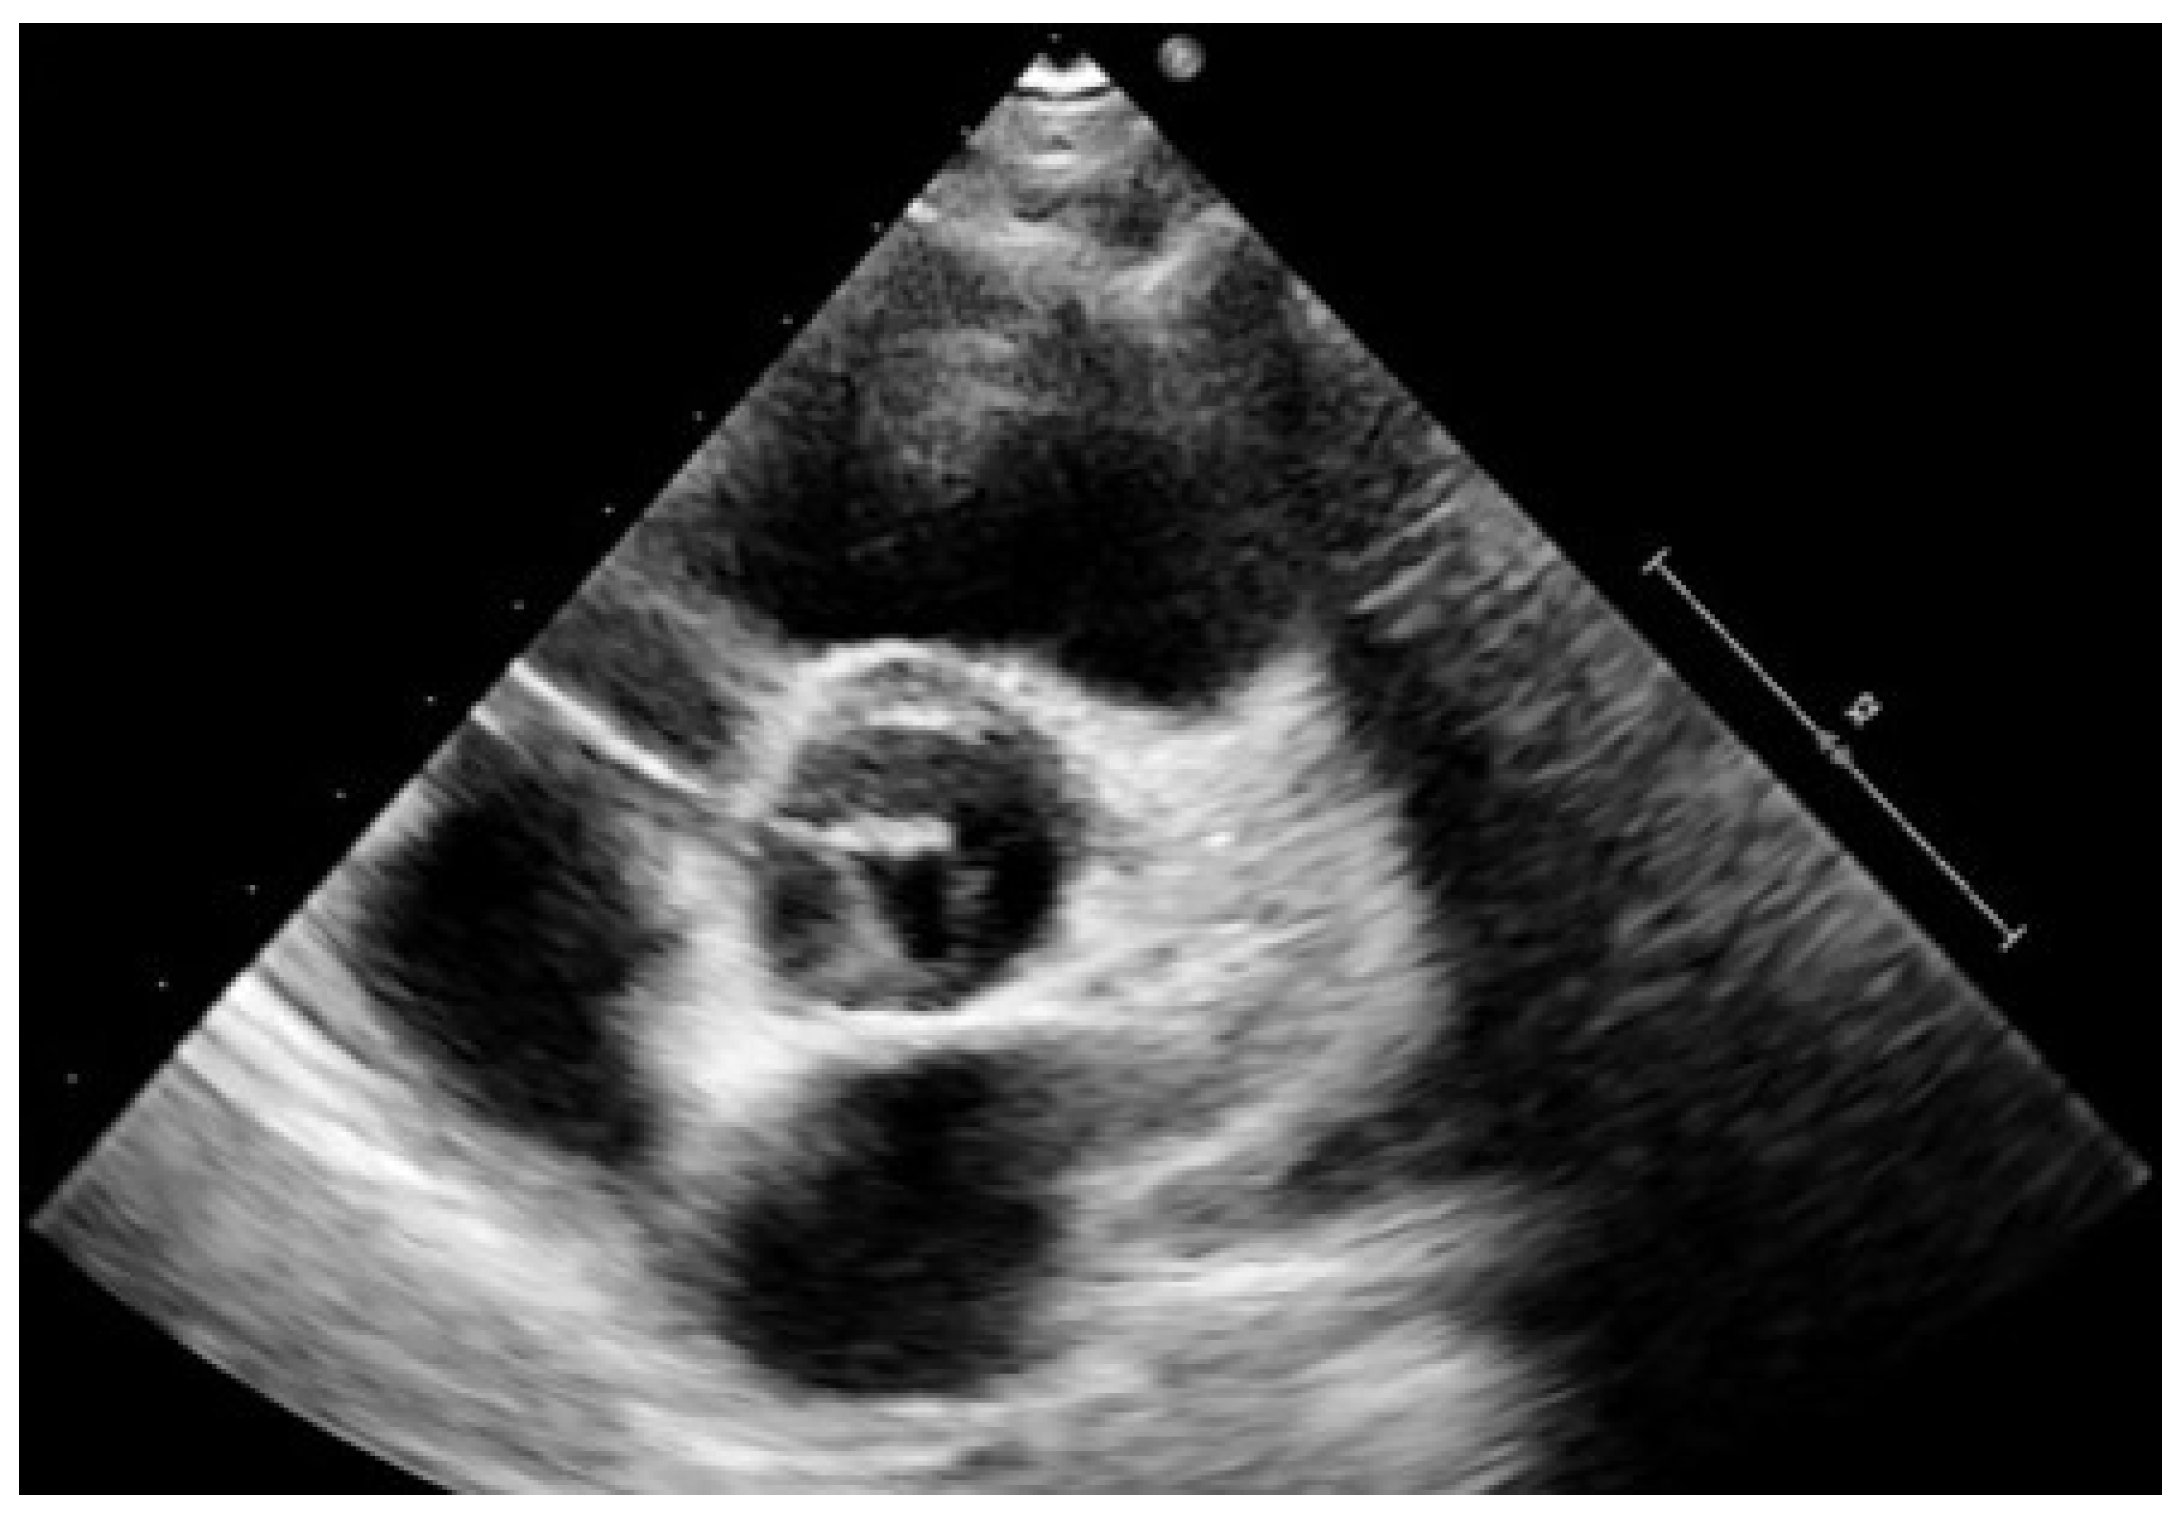

5. Diagnostic Imaging